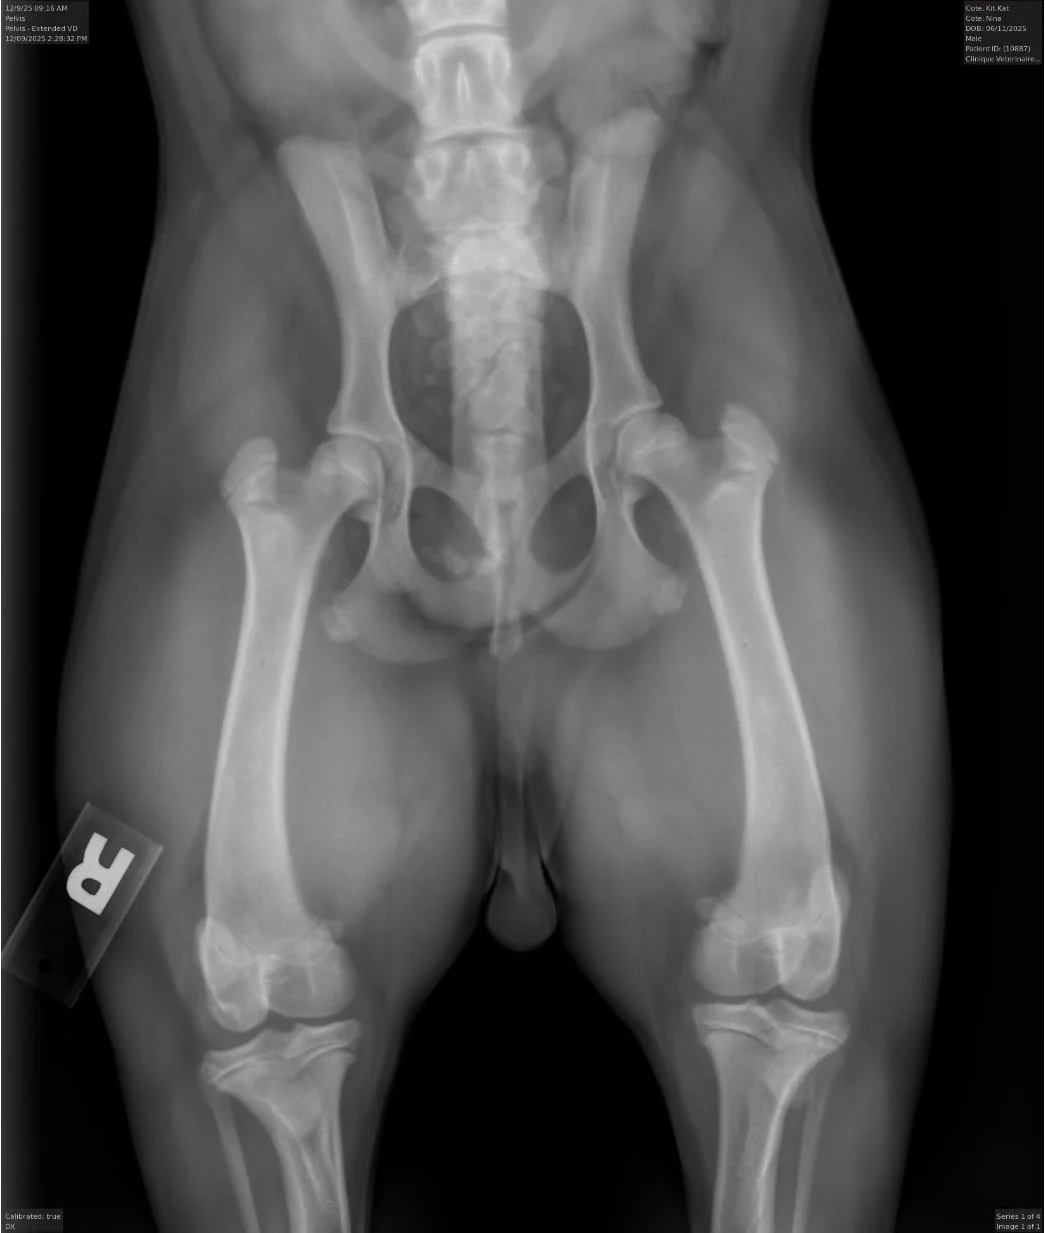

Testés OFA de la race pour Yeux, Hanches, Coudes & Colonne Vertébrale. Les prochains tests se font à l’âge d’un an.